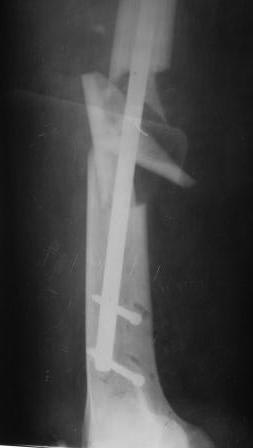

Есть ещё несколько причин, по которым «так оставлять нельзя», но пост получается слишком длинным. Не в качестве пиара, а только для пользы дела - пример из личной практики трёхнедельной давности.

Переломы обоих бёдер фиксированы стержнями той же фирмы, что и в обсуждаемом случае. Остеосинтез обоих бёдер выполнен за одну операцию продолжительностью 2 часа 40 минут. Положение больного на боку на обычном хирургическом столе. Репозиция отломков в «custom-made» спицевом репозиционном аппарате на двух спицах с корректором угловых деформаций. Определение точки ввода и проведение спицы, как правило, с первой попытки с помощью «custom-made» прицельного устройства. Рентгеновский снимок только для подтверждения расположения спицы. Ни на одном этапе операции режим прямой флюроскопии не используется. Введение стержня на уже репонированном переломе. Самое дистальное отверстие в стержне предварительно до операции рассверлено до диаметра 6,55 мм и при дистальном блокировании в него вводится по предварительно проведенной спице канюлированный блокирующий винт диаметром 6,5 мм той же фирмы. Введением такого винта решается сразу три задачи. Во-первых, исключается «шат» во фронтальной плоскости, поскольку разница между диаметром отверстия и диаметром винта всего 0,05 мм и во-вторых, отпадает необходимость во введении винта в сагитальной плоскости, и в-третьих, он способен без проблем держать нагрузку при ходьбе. Дистальное блокирование с помощью «custom-made» механического прицельного устройства, не требующего не только режима прямой флюроскопии, но и вообще рентгенологического подтверждения попадания блокирующих винтов, что значительно сокращает время вмешательства. Соответствующее дистальному и проксимальное блокирование, чтобы обеспечить больному сразу полную нагрузку на ноги. Вертикализация больного на пятые сутки после операции, контрольная рентгенограмма, которую вы видите, на двенадцатые сутки перед выпиской. Больной был уже неделю на ногах. Понимаю, что у каждого доктора свой опыт и предпочтения в выполнении блокированного остеосинтеза и свои представления о нём. Мы пользуемся именно такой методикой и техникой, к которым мы шли более десяти лет и которая на протяжении десятков операций даёт предсказуемые результаты лечения в виде отсутствие деформаций и несращений. Но, как известно, на вкус и на цвет товарищей нет. Правда у каждого своя.